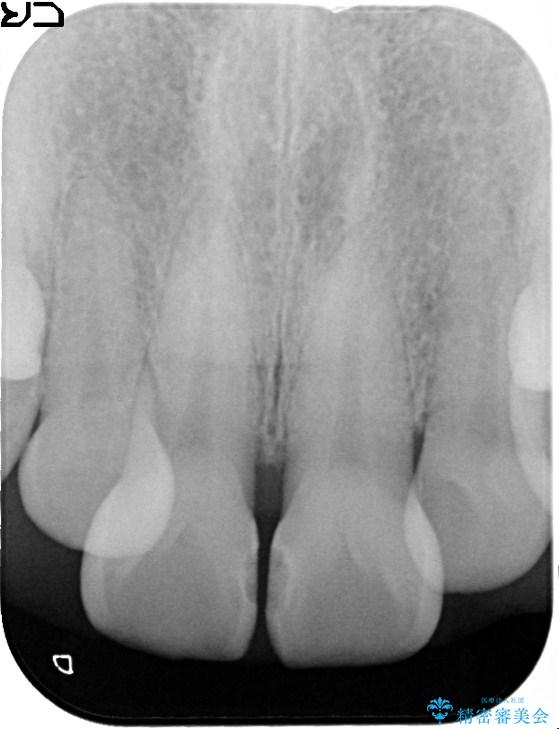

上下ともに軽度の叢生があり、下顎がやや前突傾向にあったため、本来であれば矯正治療が第一選択となります。矯正によって下の前歯を後方に移動させることで、咬み合わせの改善とともに前歯のデコボコも整えることができます。

上下に叢生(歯のデコボコ)と反対咬合があるため、本来であれば矯正治療が最も理想的な治療選択となります。